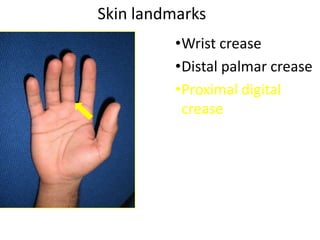

- Naming the bones, joints, tendons, nerves and skin landmarks of the hand and wrist.